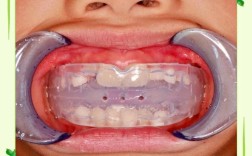

地包天(反颌)是一种常见的牙齿错颌畸形,表现为下牙覆盖上牙,影响美观和咬合功能,矫正方法因年龄和严重程度而异:儿童期可通过活动矫治器、功能矫治器或前方牵引促进上颌发育;青少年及成人则多采用固定托槽(金属/陶瓷)或隐形矫治器(如隐适美)调整牙...